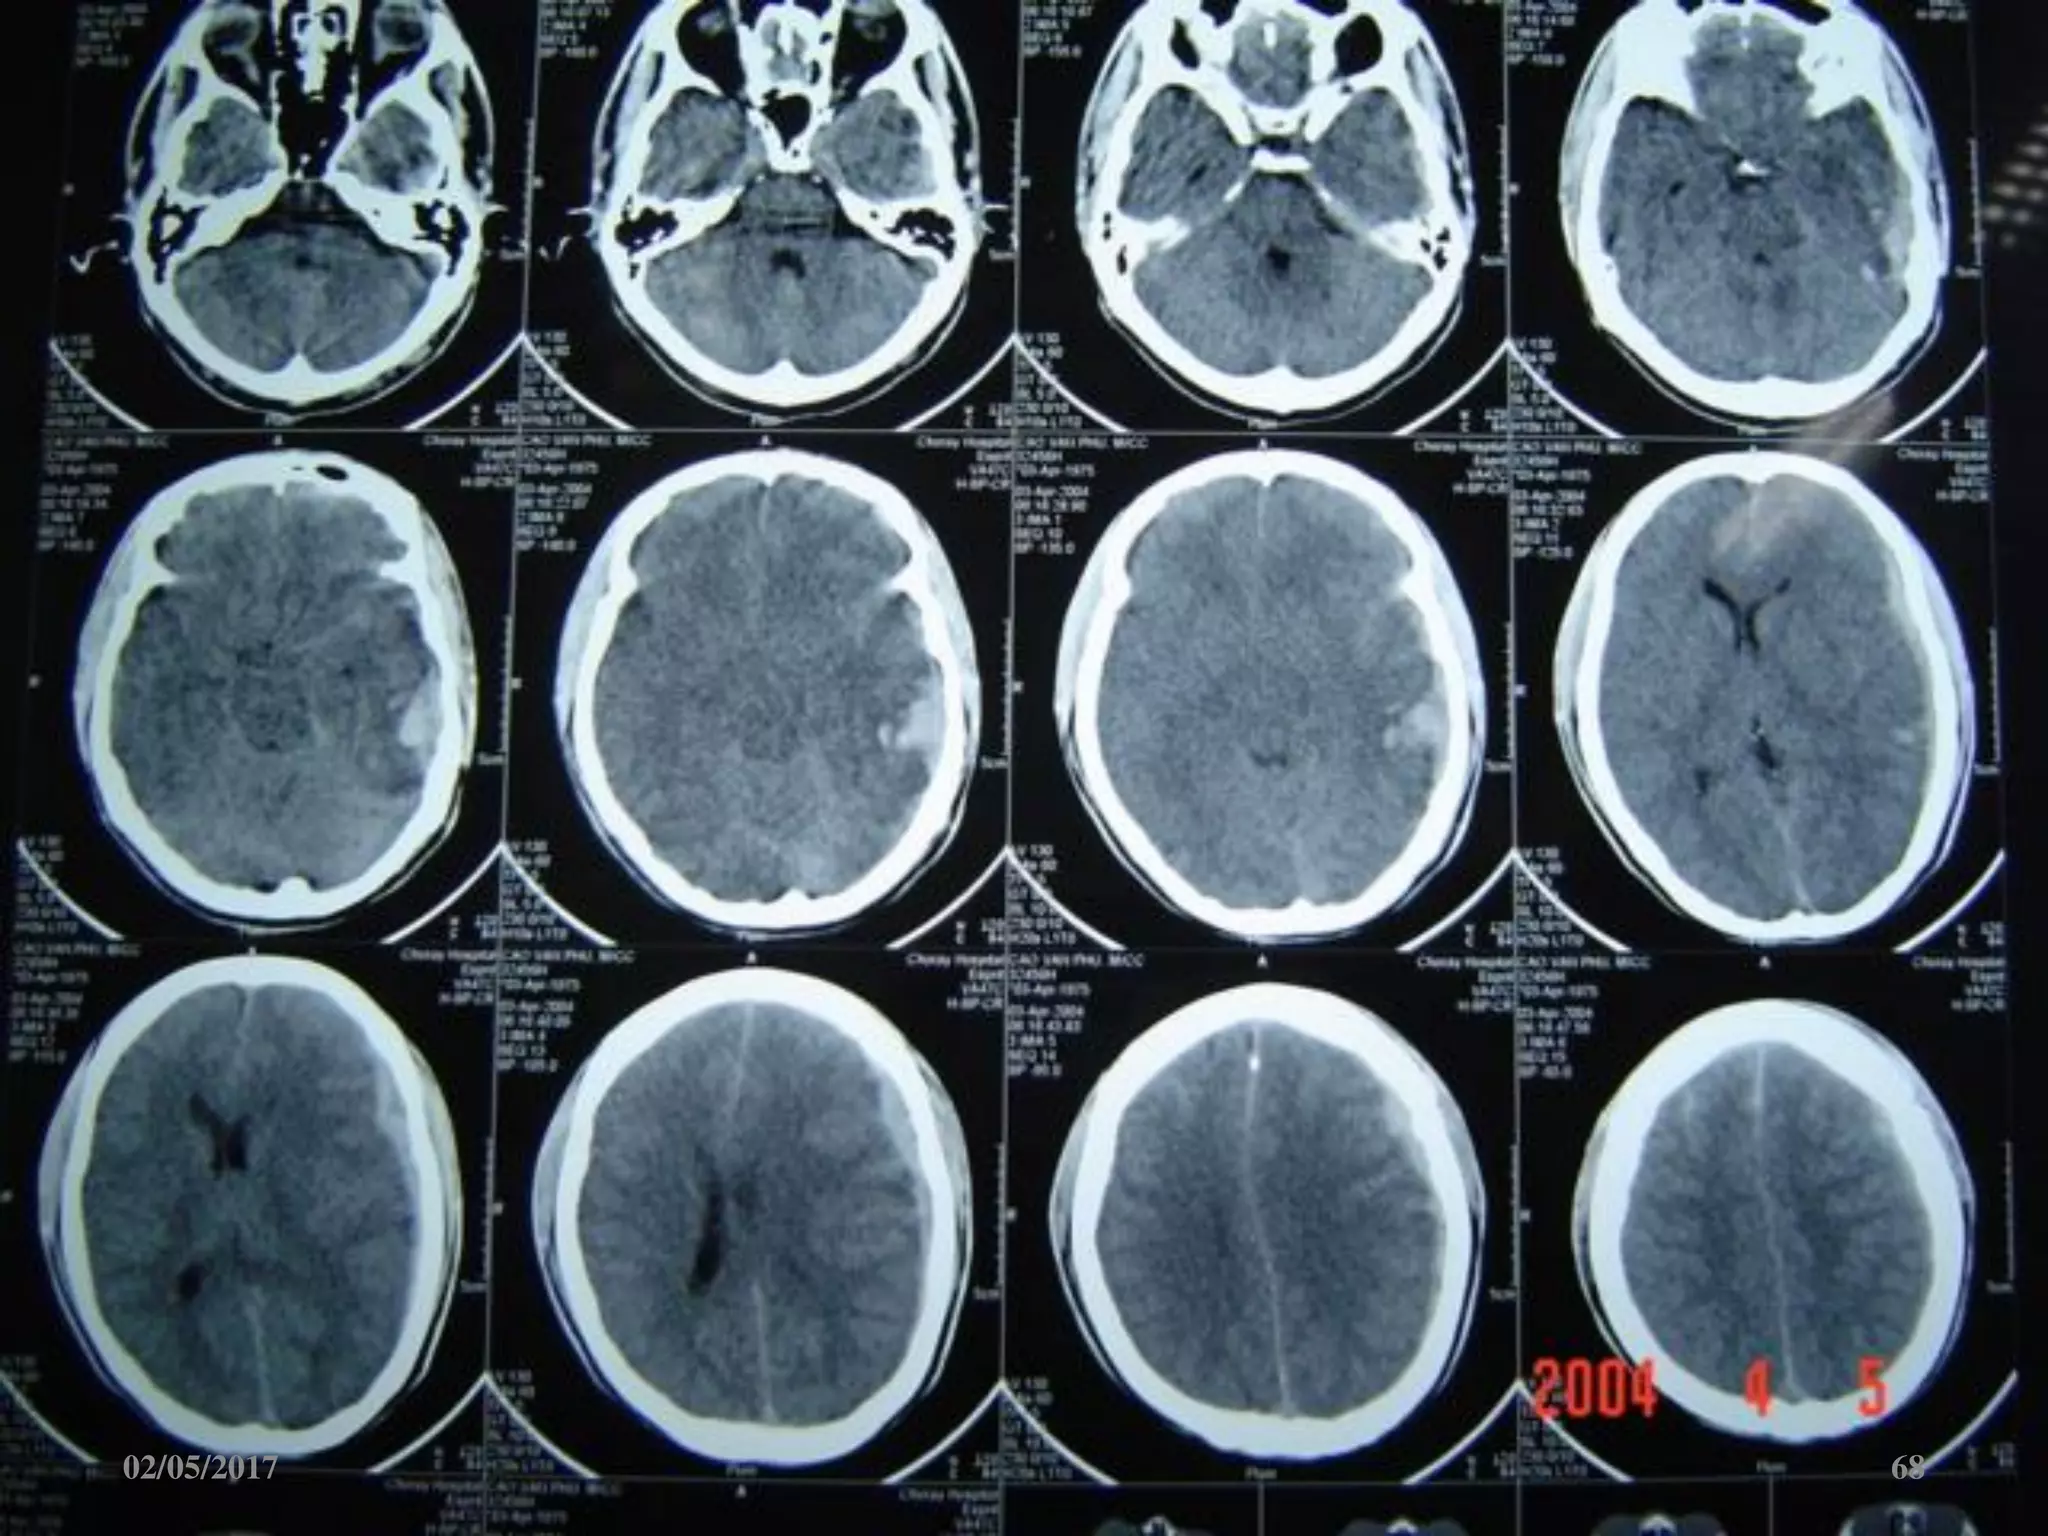

Phù não

• Giảm đậm độ lan tỏa.

• Mất ranh giới chất

trắng-xám.

• Xóa các rãnh não-bể

não.

• Não thất 2 bên nhỏ.

02/05/2017 67

02/05/2017 68